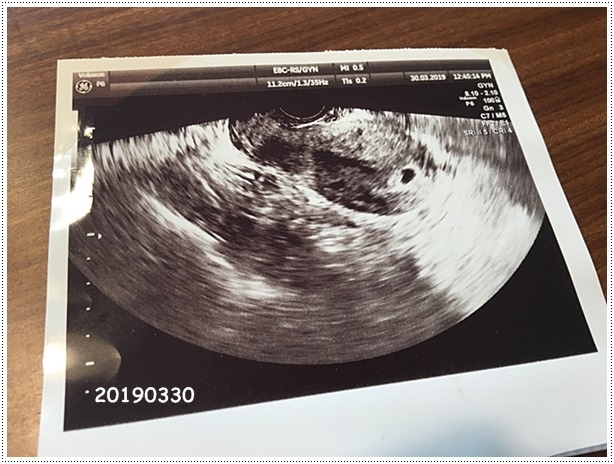

20190330

懷個孕,一個禮拜看了三次醫生,有夠奔波的

禮拜六早上打了電話確認李婦產科有看診,趕緊飛奔過去,早上看診的是李正義醫師,久仰他的大名,第一次見到他,問診的時候很仔細親切,覺得李婦產科裡面的醫生都滿不錯的,大概是懷孕初期的關係,醫生要幫我照陰超,這這這,上次禾馨照痛死了,所以我很排斥,還跟醫生說禮拜三在婦幼照到了,應該可以照腹超,醫生也從善如流,但,這次又是一個照不到,怎麼每次CC陪診,都照不到寶寶,只好再次挑戰陰超,照的時候醫生還要我不要怕,不會有疼痛感,ㄟ果然李醫師技術比較好,沒什麼感覺就照完了,跟上次在禾馨照根本天壤之別啊啊啊啊

醫生這次不但說寶寶位置正確,還說他落點很好,YAYA好開心,

沒什麼事比寶寶健康更重要的了

請醫生開了中英文的不適航證明,